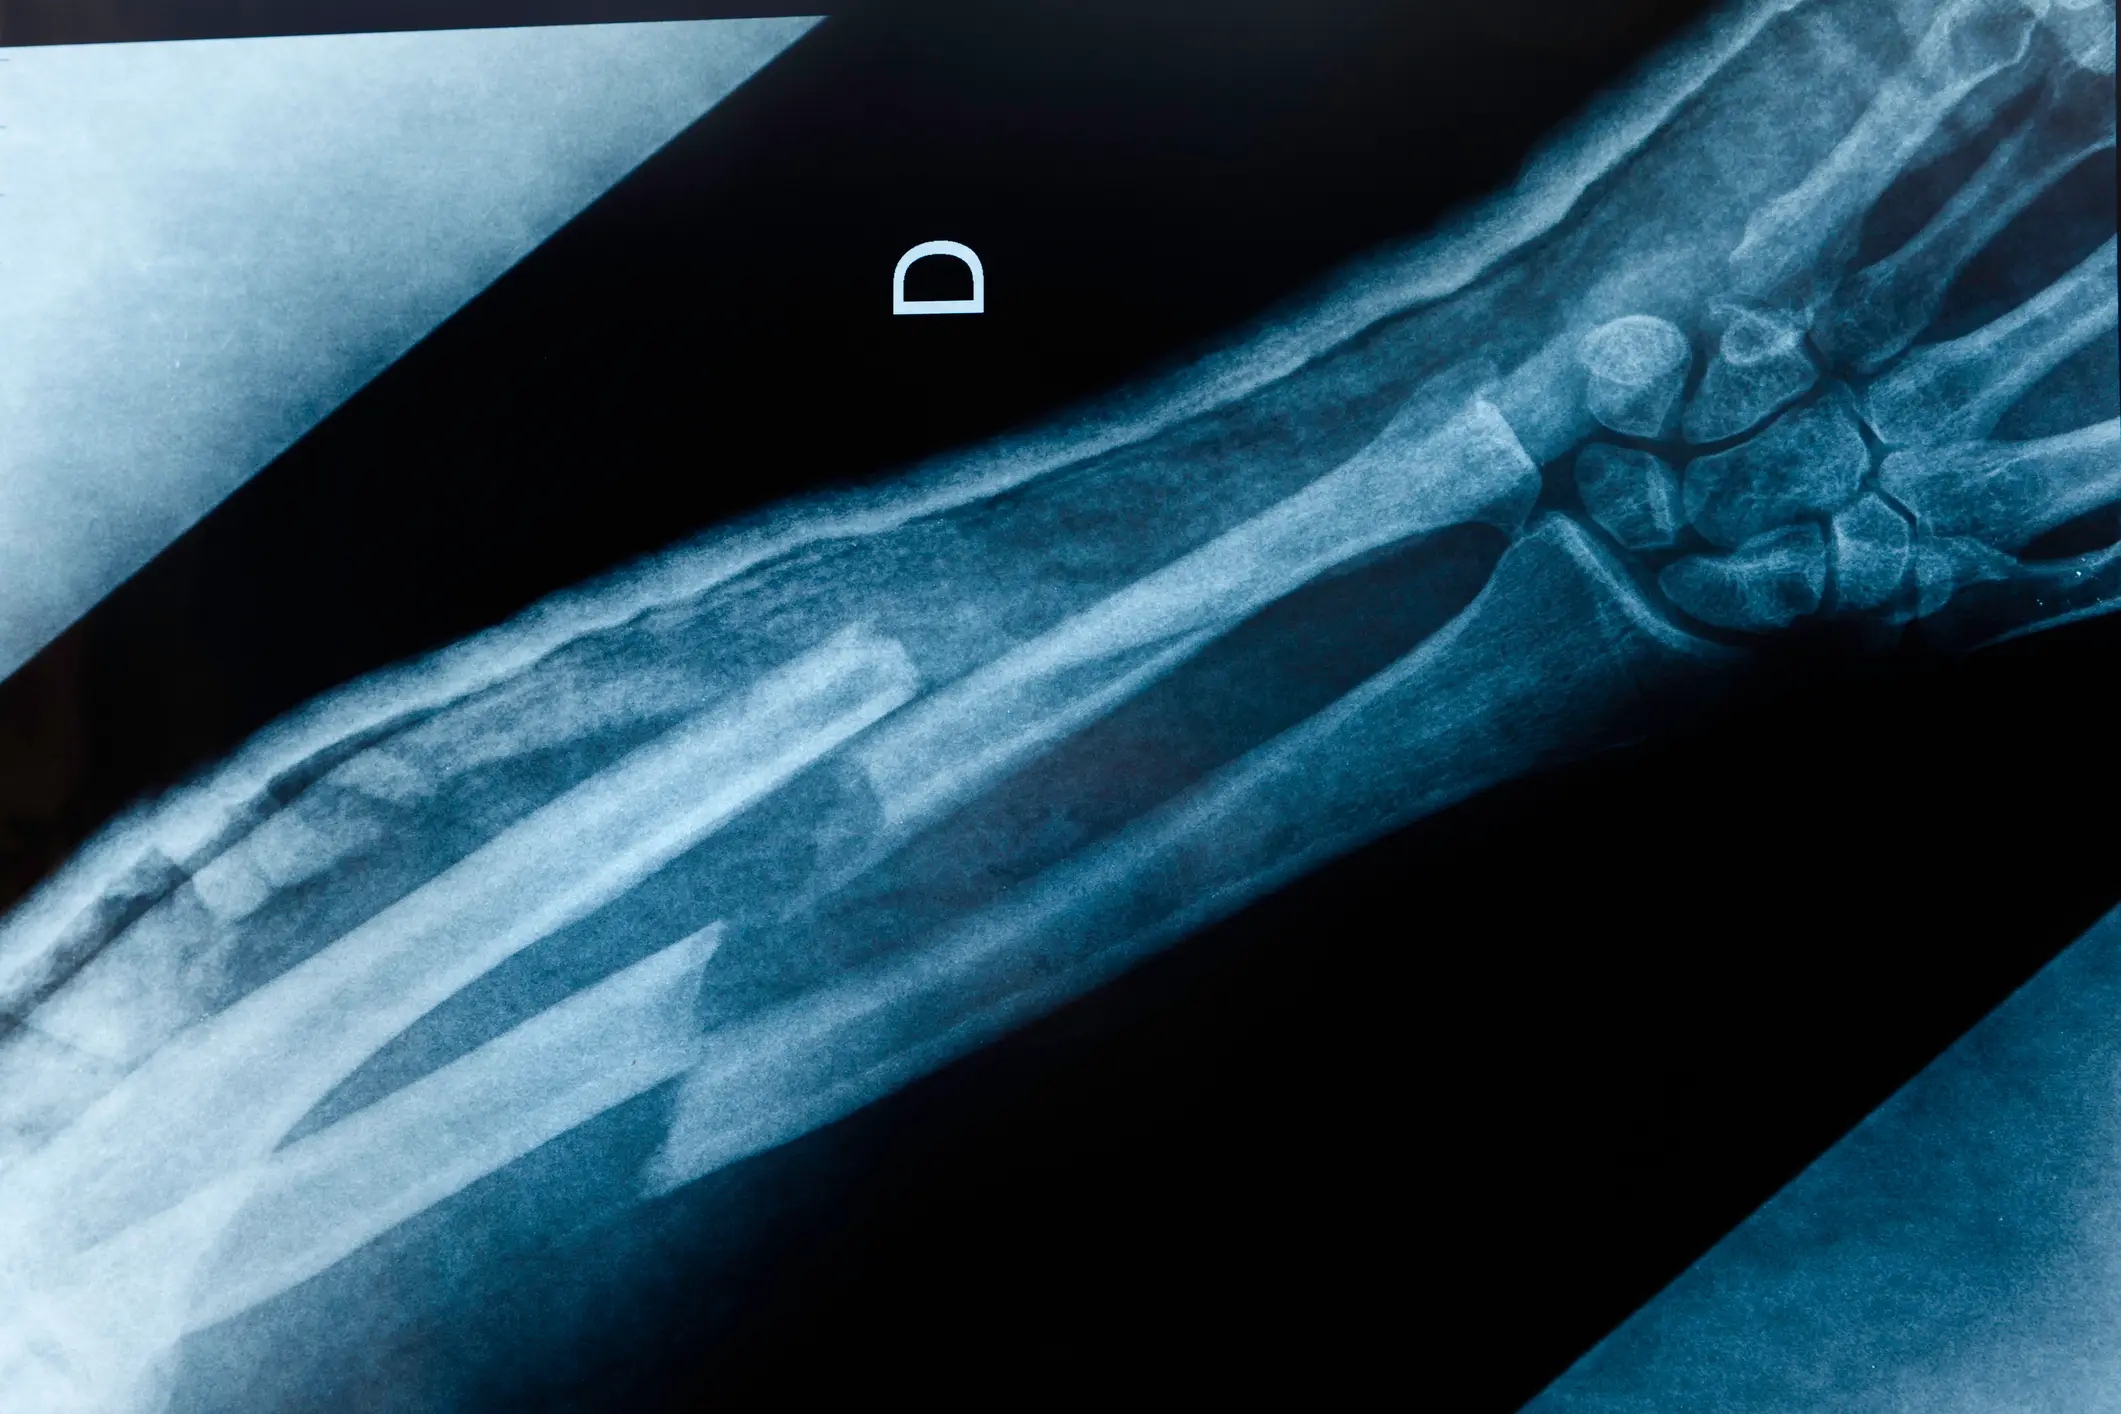

Osteoporosis is a condition that causes a loss of bone density, and those with it are more likely to experience bone fractures.